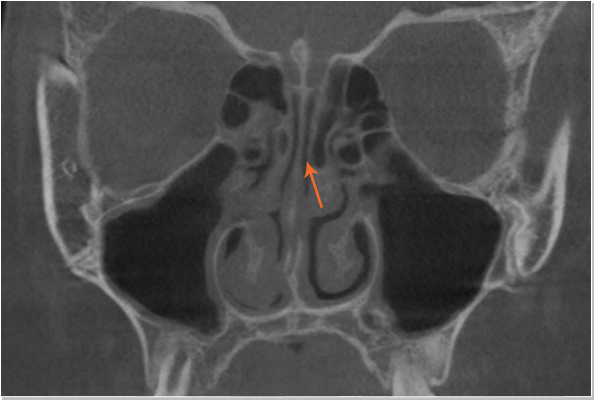

코의 내부구조

낮은코 내부구조 CT 사진 비중격 만곡증

낮은코 내부구조 CT 사진 커져있는 코덧살(비염)

비중격만곡증 교정술, 고주파 비염수술로 코의 기능을 회복시킴

절골술 및 비중격만곡증 교정술로 휘어진 코 교정